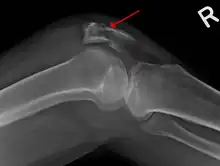

A fracture of the patella seen on a lateral view

SpecialtyOrthopedics